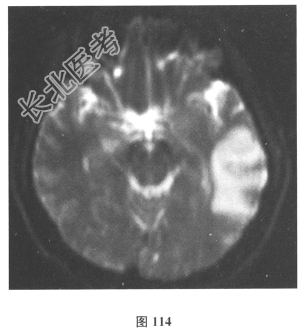

- 简答题2、脑脊液检查:常规、生化均正常,CSF-病毒TORCH(-),抗Hu、Yo、Ri均阴性,OB、MBP正常。血清抗Hu、Yo、Ri均阴性。颅脑MRI显示左颞枕、右顶枕多发长T₁、长T₂信号,Flair高信号,病变累及皮质及皮质下白质,病灶无强化,见图108~图114。根据颅脑MRI,需要鉴别的疾病应是